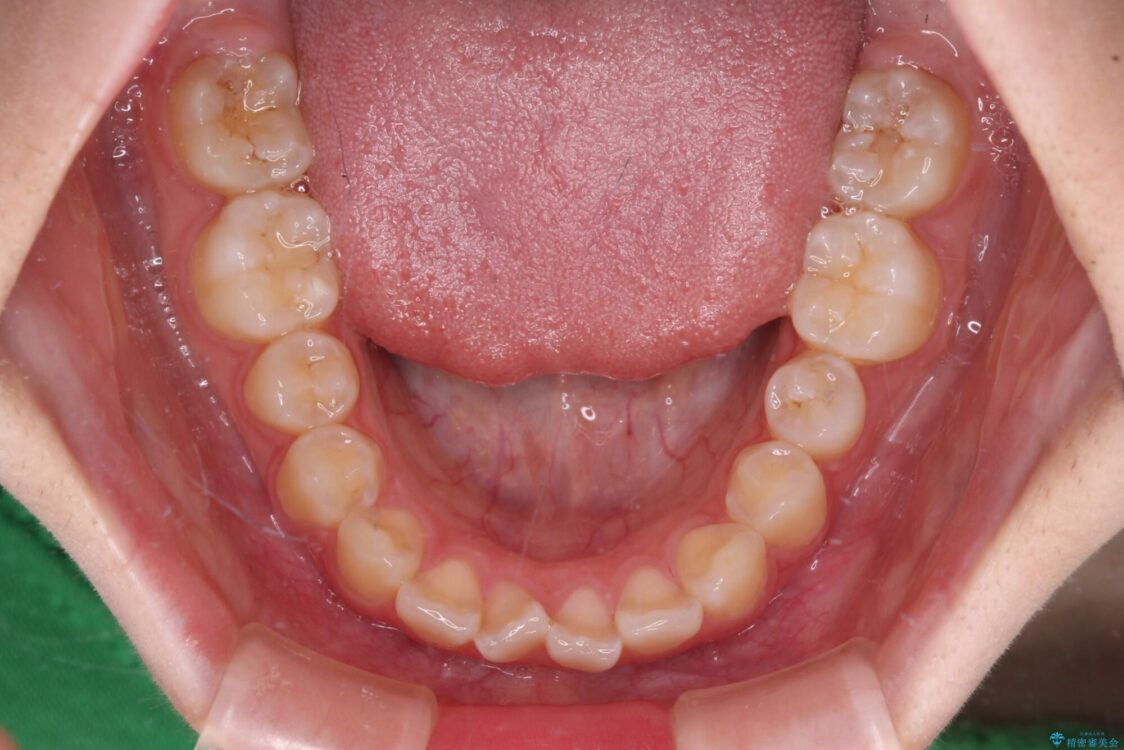

上下前歯のねじれを気にして来院された患者様です。

ワイヤー矯正でもマウスピース矯正でも対応可能でしたが、マウスピース矯正の自己管理が面倒であること、上顎前歯の捻転が著しいことから、ワイヤー矯正での治療を希望されました。

治療前

• インビザラインは使える自信がない ワイヤー装置にて矯正治療 治療前画像